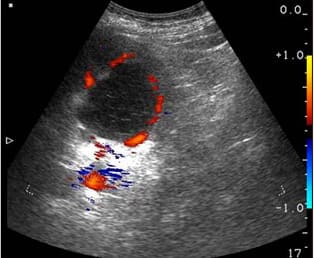

Вторият случай е свързан с киста с диаметър 3 cm. Болестта обикновено преминава без симптоми. Не боли, резултатите са добри, уринирането протича гладко. Ето защо кистата беше толкова голяма. 22-годишното момиче се страхуваше от операция. Изписахме й Nefro Aktiv . В рамките на месец повторният преглед не показа никаква патология.